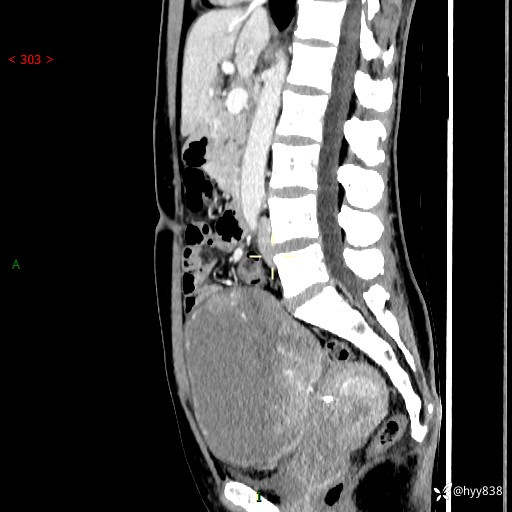

【患者信息】:女,50岁

【主诉】:外院超声发现腹盆肿块,为进一步诊治来我院,门诊已“盆腔肿块”收入院。

腹盆CT平扫+增强

【临床诊断】:盆腔肿瘤